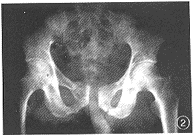

例2男,46岁。1998年1月15日因外伤致左侧坐骨、耻骨支骨折,骨盆X线片示,骨折移位,左侧闭孔变形(图2),嘱其卧床休息。3周后,逐渐出现左股内侧疼痛,放射至膝内侧上方,股内侧皮肤感觉迟钝,夜间出现股内侧肌颤,咳嗽时症状加重,左闭孔处有深压痛,并向左股内侧放射。诊断:左坐骨、耻骨骨折继发左闭孔神经卡压综合征。给予质量分数为2%的利多卡因3ml、醋酸泼尼松龙50mg封闭治疗,每周1次,共5次。因疗效不明显而行闭孔神经探查术。术中见左耻骨骨折的两断端及瘢痕嵌压闭孔神经。切除瘢痕及部分闭孔膜,并切断闭孔外肌的一部分,充分松解闭孔神经及闭孔动脉。术后第2d,股内侧疼痛消失,2周后感觉逐渐恢复。

图2 骨盆X线片示,左坐骨、耻骨支骨折,闭孔变形